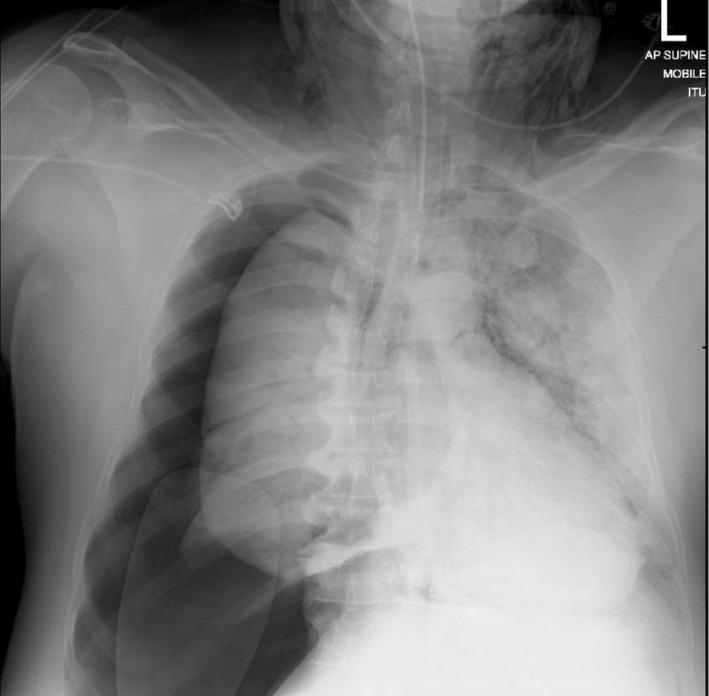

When using a gum elastic bougie, a common device to aid difficult intubations, one must appreciate the significant consequences, be prepared to manage emergency complications, and use safely by advancing under direct vision and using the markings to guide insertion.